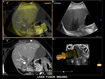

• In USA contrast is only approved for use in liver